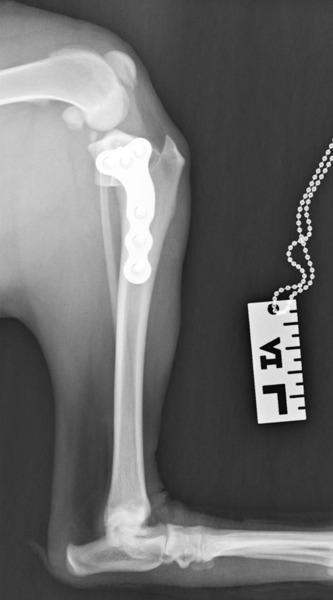

Dr. Maloney has a passion for and special training in surgery. She is experienced and adept at TPLO procedures for treatment of cranial cruciate ligament rupture, laryngeal lateralization for laryngeal paralysis, ventral bulla osteotomies for aural polyps in cats, as well as a wide variety of other soft tissue and orthopedic surgeries.